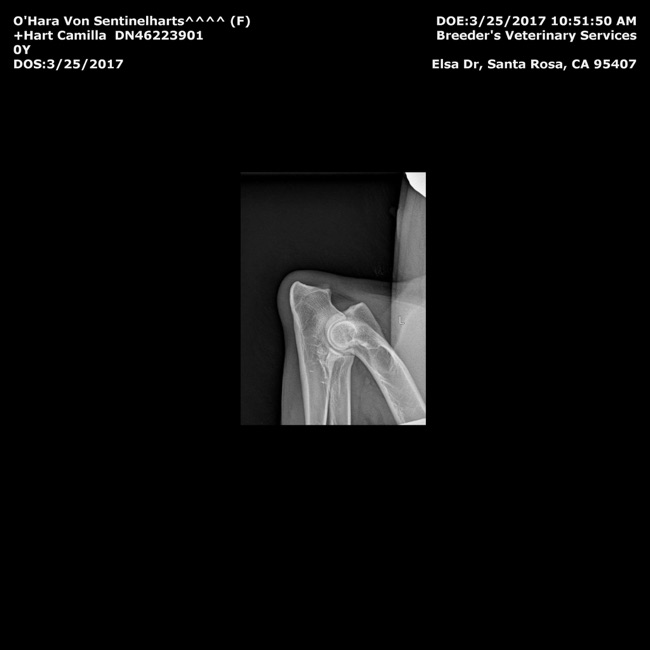

Hips- OFA GOOD GS-99766G24F-VPI

Elbows- OFA Normal  GS-EL38352F24-VPI